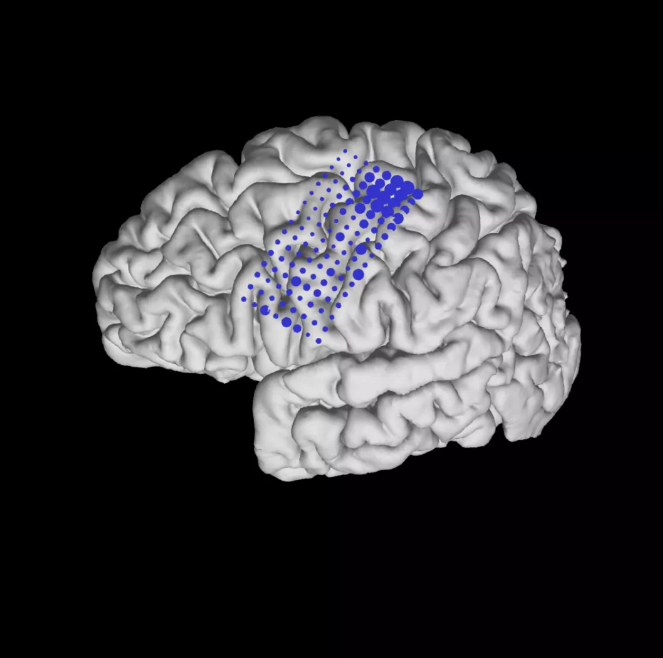

a,游标控制管道。参与者大脑MRI上覆盖的ECoG电极(按解剖区域着色)的图示。在速度卡尔曼滤波(KF)解码器中,将ECoG信号连续流、滤波并合并到神经特征中。解码器权重是通过闭环解码器自适应过程(CLDA)学习的。S1,初级体感皮层;M1,初级运动皮层;PMC,运动前皮层;PMV,腹前运动皮层;和SMA,辅助运动区域。